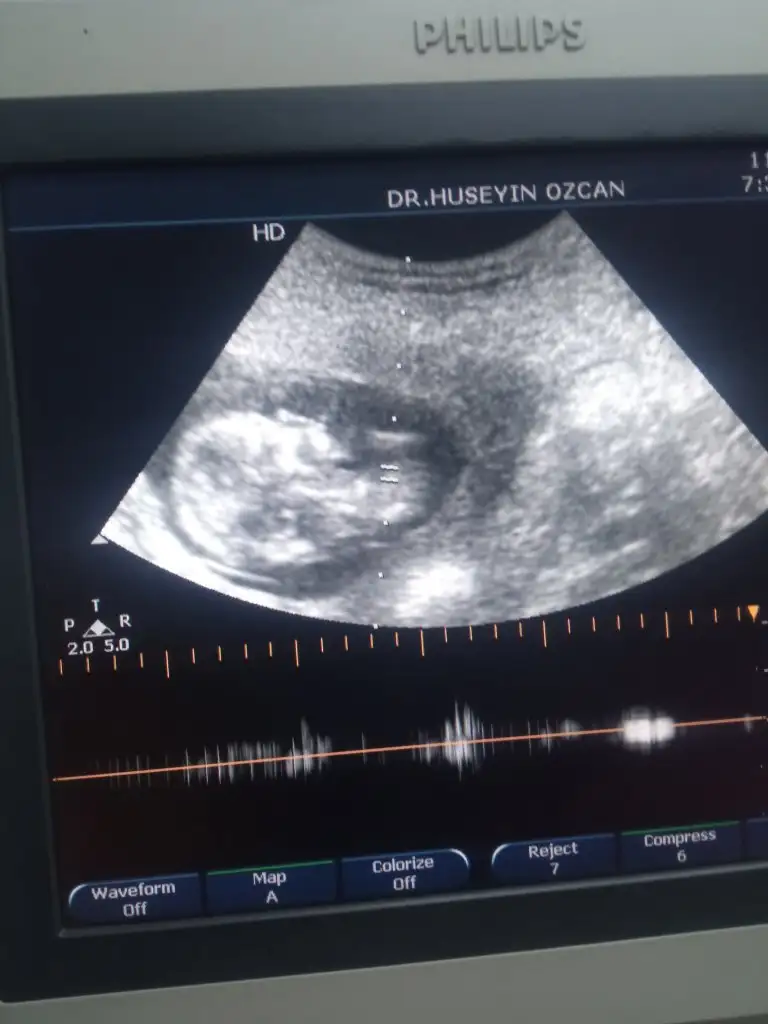

Ikra meyra Canım merhaba 10. Haftamda bakmıştın erkek , emin olmak için 12. Haftada bakalım demiştin 13+0 karından ultrason fotomuzu atıyorum halen fikrin aynı mı ? Teşekkür ederim